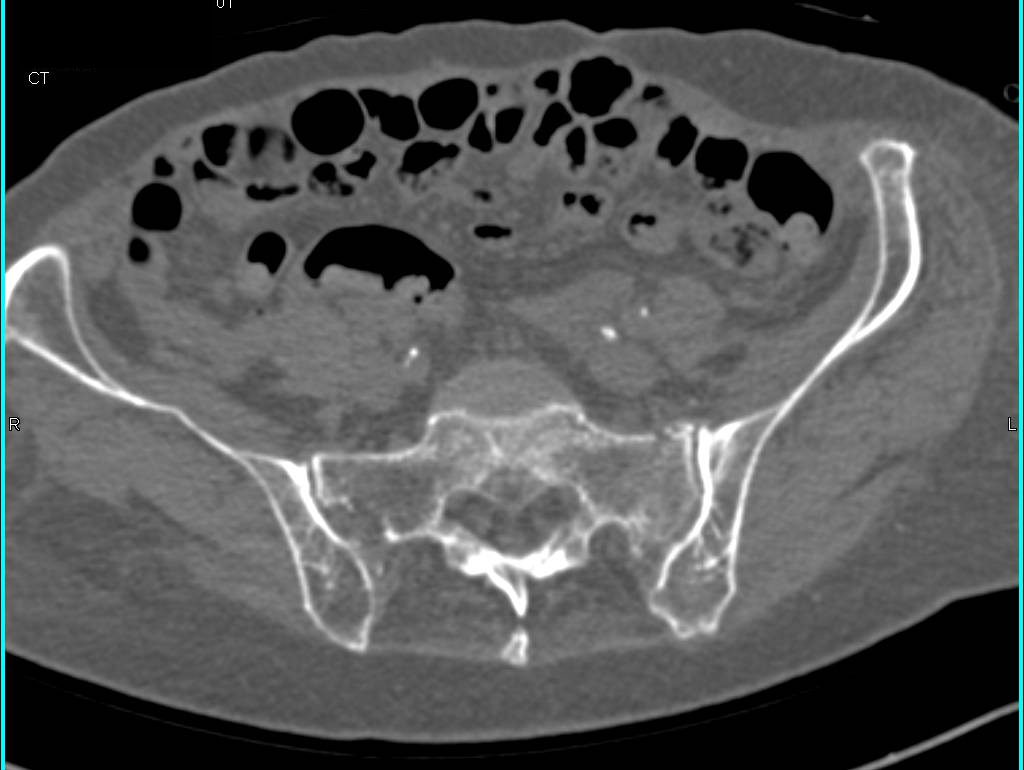

Fracture of the Left Superior and Inferior Pubic Ramus Plus Sacral Fracture